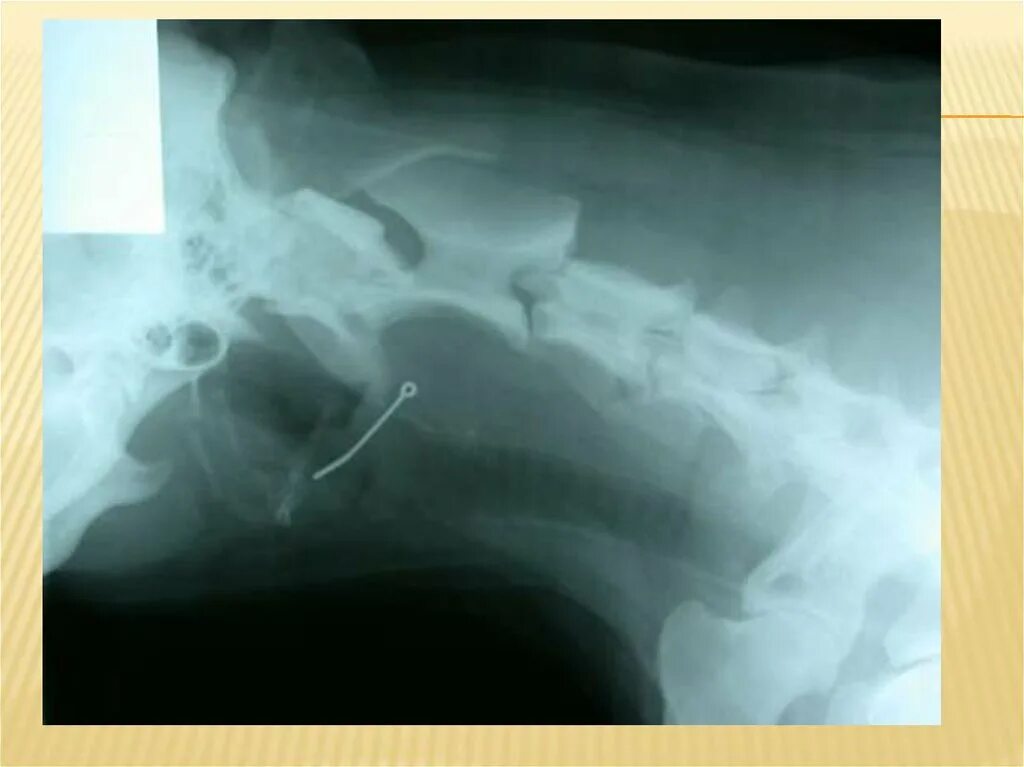

Заметить внутрь